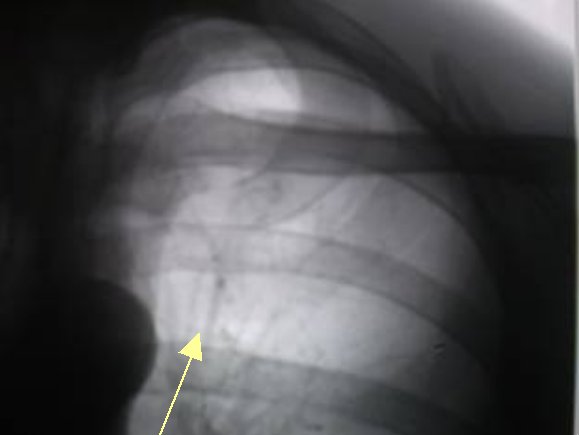

Протокол. На прямой цифровой флюорограмме органов грудной полости (1), произведенной в прямой стандартной проекции слева в 1 межреберье дифференцируется малоинтенсивная очаговоподобная тень. При цифровой обработке изображения (2) – эквилизация, увеличение в два раза, вышеописанная тень неправильной овальной формы, малой интенсивности с нечеткими контурами. На томограммах – оптимальный срез 11 см. (3, 4) на уровне 1 ребра определяется крупноочаговая тень размерами 1,0 х 0,8 см. средней интенсивности, почти однородной структуры с неровными, нечёткими контурами за счёт мелкой лучистости по контуру.

2. цифровая обработка изображения – эквилизация, увеличение в два раза